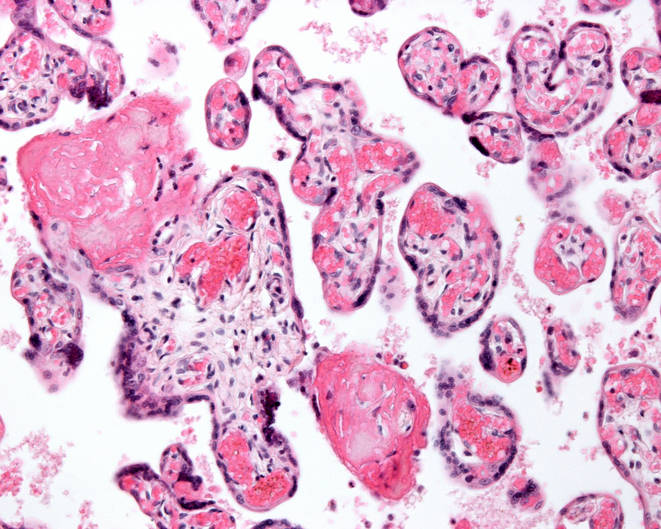

Une maladie inflammatoire du placenta serait à l'origine de fausses couches à répétition

Dans certains cas rares, ces pertes se répètent, sans cause clairement identifiable. Des médecins du CHUV et de lʹUNIL décrivent une approche thérapeutique inédite pour des femmes souffrant de pertes de grossesse à répétition liées à une maladie inflammatoire très rare du placenta.